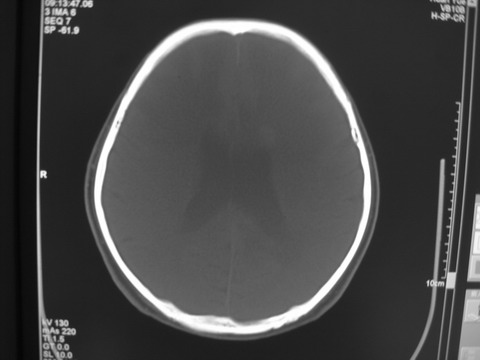

患者 男 69岁 头晕头痛不适

多发病灶,指状水肿,首先诊断转移瘤。

多个结节并周围大面积水肿区,多考虑多发性脑转移瘤

小病灶、大水肿,病灶多发,首先考虑多发转移瘤;建议查原发灶。

额顶叶多发小病灶、大水肿,首先考虑多发转移瘤;建议查原发灶

脑内多发病灶,小病灶,大水肿。

典型转移性肿瘤。

应进一步检查,查找原发病灶。

结果 : 该患者结肠癌病史5年 考虑脑转移